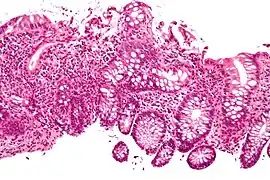

Micrograph showing cryptitis in a case of Crohn's disease. H&E stain.

In histology, cryptitis refers to inflammation of an intestinal crypt.

Cryptitis is a non-specific histopathologic finding that is seen in several conditions, e.g. inflammatory bowel disease,[1] diverticular disease,[2] radiation colitis,[3] infectious colitis.